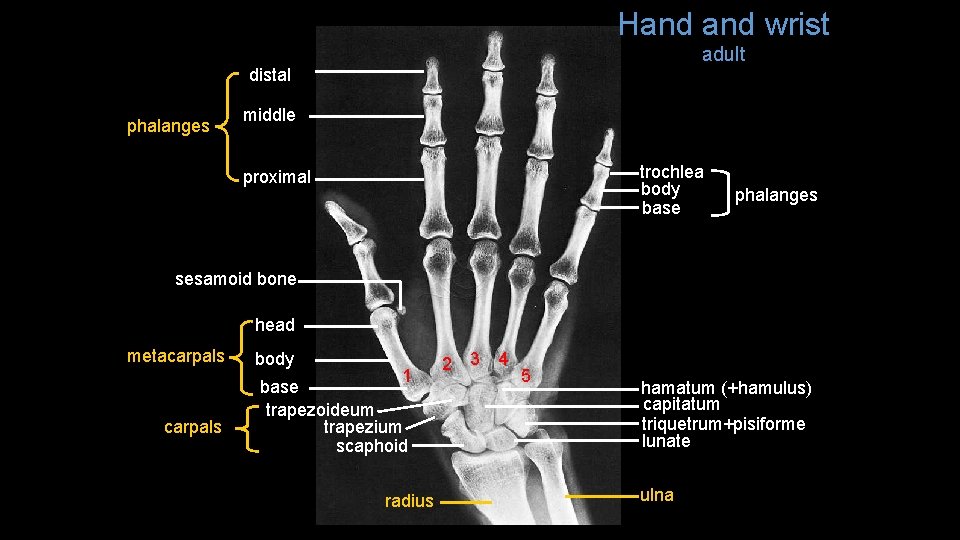

Hand wrist adult distal phalanges middle trochlea body base proximal phalanges sesamoid bone head metacarpals body 1 base trapezoideum trapezium scaphoid radius 2 3 4 5 hamatum (+hamulus) capitatum triquetrum+pisiforme lunate ulna